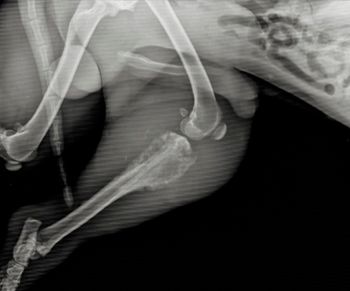

Experts share pearls of wisdom to avoid complications during surgical procedures